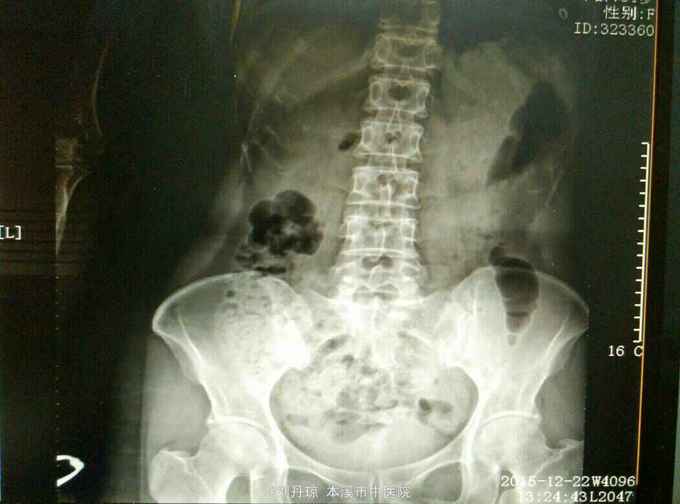

腰痛伴有右下肢放射痛三年,加重十天。患者三年前因抬重物腰部刺痛,休息一周后好转,十天前因开车劳累4.5小时后又洗澡,第2天即感右下肢放射痛难以忍受,遂由门诊收入院治疗。

查体:L5—S1棘突旁压痛阳性。直腿抬高实验。左70度,右30度。加强试验左侧阴性,右侧阳性。腰椎功能障碍。CT:L5—S1椎间盘突出。